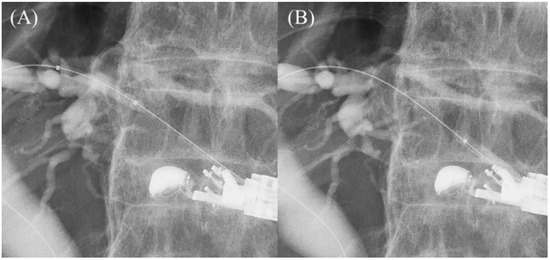

5.6. Stent Deployment